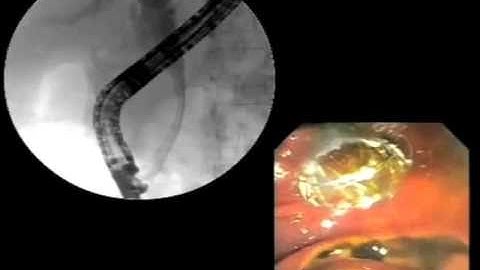

Severe cholangitis - Biliary wall stent placement